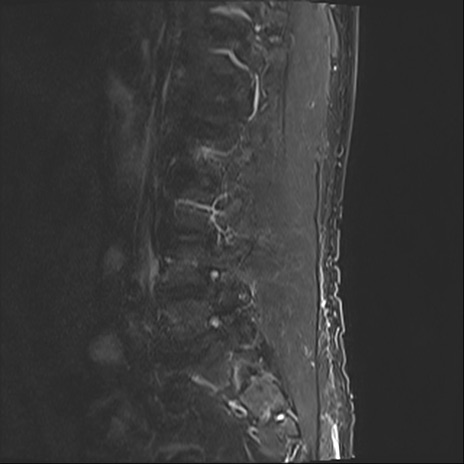

【整形】TIPS症例2 腰椎MRI STIR(矢状断像)

【症例】70歳代男性

【主訴】左下肢痛

【現病歴】2週間前くらいから腰痛、左下肢痛あり。左臀部から大腿、下腿外側のしびれが常時ある。歩行とともに同部位の痛みあり。

【身体所見】Lasegue70-/60+、Bragard-/±、PTR ±/±、ATR -/-、IP 5/5、TA 5/4、TS 5/5、EHL 右第1足趾なし/3、FHL 5/5、hypersthesia(-)、足背動脈触知良好

異常所見と診断は?